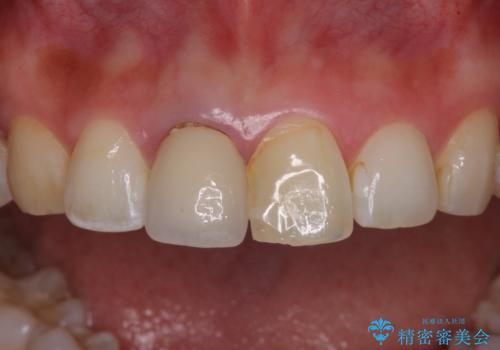

- 前歯のプラスチックが変色していることを気にして来院された患者様です。

反対側同名歯にセラミッククラウンが装着されていたため、そちらのクラウンと形態や色彩を揃えるようオーダーメイドタイプのオールセラミッククラウンにて補綴することとしました。